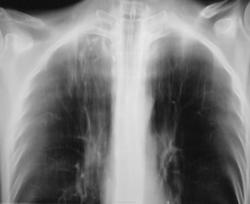

Инфильтрация. Скорее всего ТБЦ.

Направлять к фтизиатру?